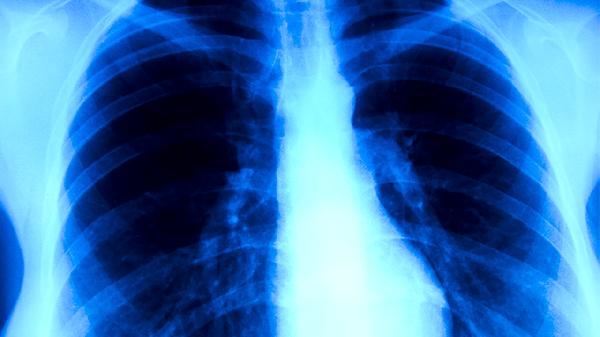

当鼻病毒感染合并细菌感染或患者存在免疫功能缺陷时,病毒可能突破上呼吸道屏障。这种情况下病毒可侵袭支气管和肺泡,导致间质性肺炎或病毒性肺炎,临床表现为持续高热、呼吸急促、血氧饱和度下降等。早产儿、未控制的哮喘患者及长期使用免疫抑制剂的人群需特别警惕病情进展。